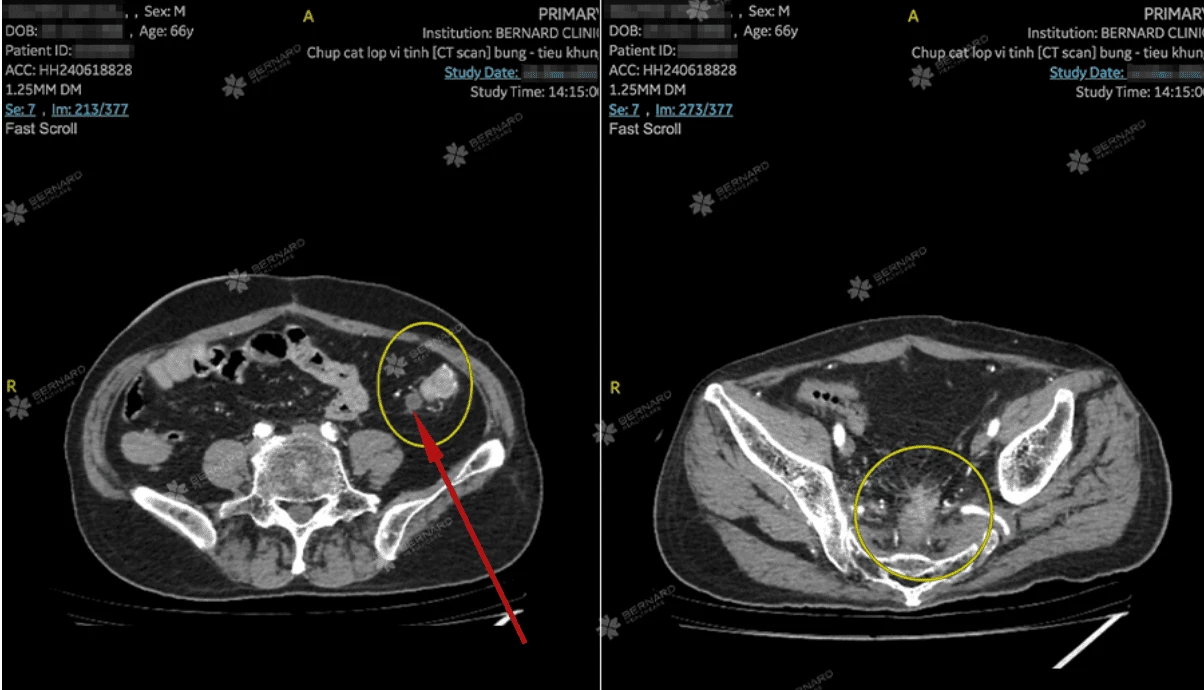

Hình ảnh CT Scan bụng - tiểu khung ghi nhận: 2 tổn thương tại đường tiêu hóa

Ở vị trí nối sau phẫu thuật, thành trực tràng dày lên bất thường, bờ không rõ ràng, nghi ngờ có khối u tái phát.

Không chỉ vậy, ở đoạn đại tràng bên trái cũng phát hiện một tổn thương bất thường dài khoảng 3,5 cm, chỗ dày nhất hơn 1 cm, xung quanh có vài hạch nhỏ (dmax khoảng 8mm). Dấu hiệu cho thấy ung thư có khả năng đã lan ra vùng lân cận và có thể di căn hạch vùng (N+). Dù chưa thấy xâm lấn sang cơ quan khác, nhưng các dấu hiệu hình ảnh học gợi ý một tổn thương ác tính cần được làm rõ.